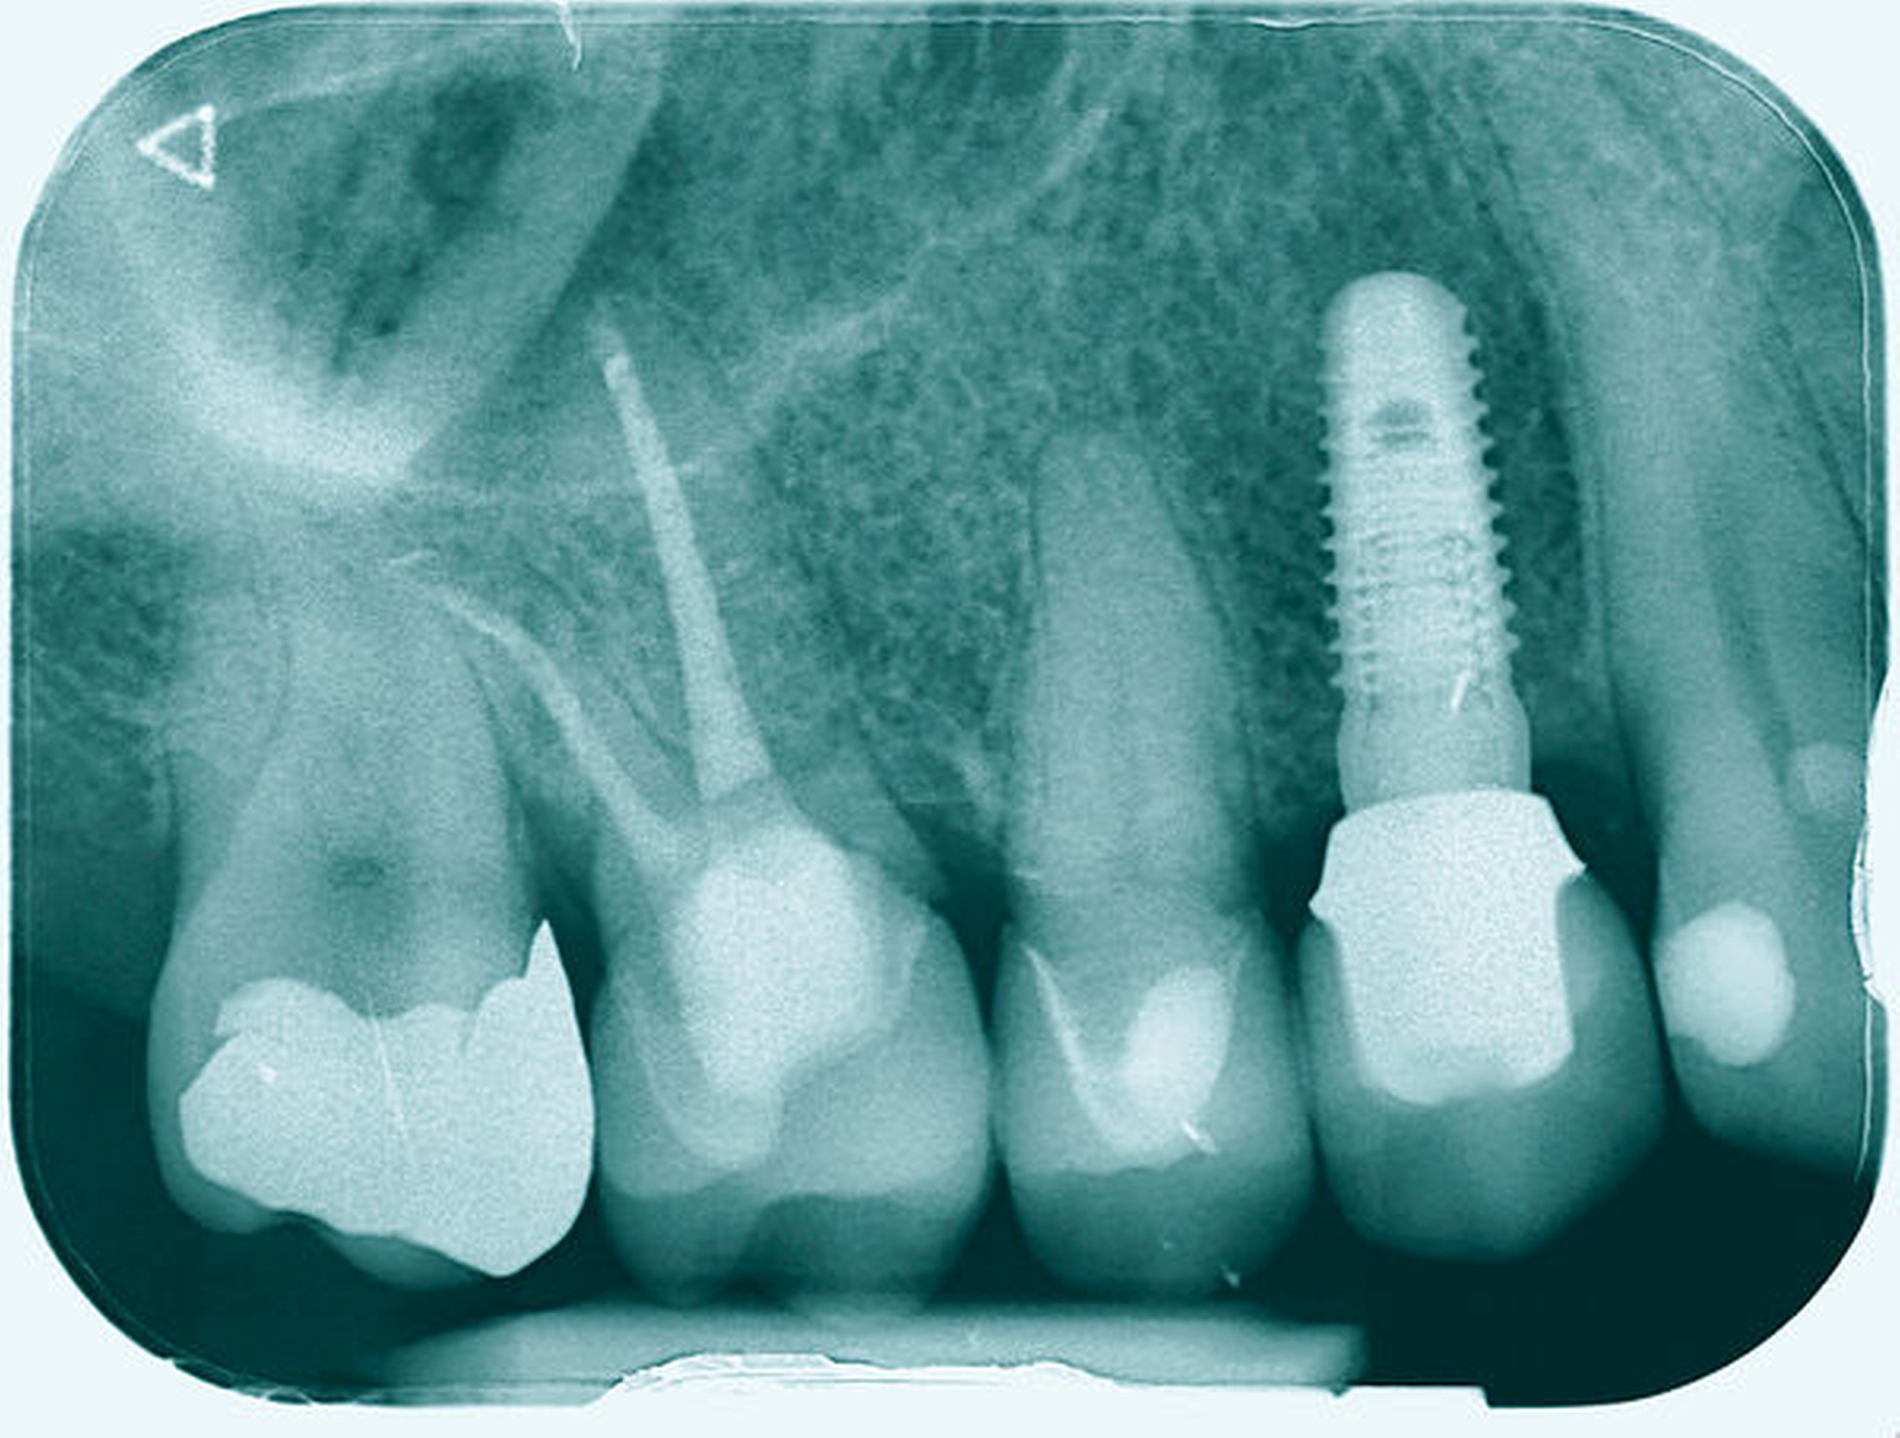

Im Rahmen der Versorgung erfolgte auch ein Austausch der Extensionsbrücke 16–14 durch Einzelkronen auf 16 und 15 sowie einer Implantatversorgung mit Einzelkrone in Regio 014. Der Erhalt des Zahnes 16 ermöglichte so eine wenig invasive Versorgung des ersten Quadranten mit guter Hygienefähigkeit. Alternativ wäre bei Extraktion des Zahnes die Versorgung beispielsweise mit einer ausgedehnten Brückenkonstruktion von 13–17 oder einem weiteren Implantat in Regio 016, vermutlich mit (indirektem) Sinuslift, notwendig gewesen. So konnte der Fall minimalinvasiv zufriedenstellend gelöst werden. Die Patientin ist seit dem Eingriff beschwerdefrei und kommt gut zurecht. Die Situation ist nun seit sechs Jahren stabil.